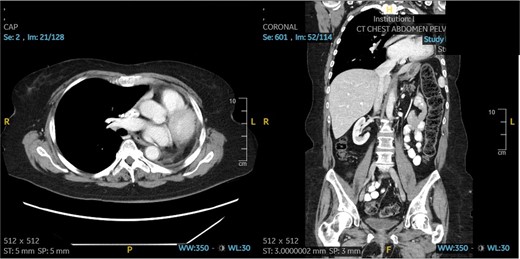

A 60-year-old woman with acute lymphoblastic leukemia recently started on chemotherapy presented to the emergency department with a dry cough that later progressed to a productive cough with green sputum. Exam was largely unremarkable as patient was afebrile and had normal lung auscultation. Initial infectious work-up, including bacterial, fungal and mycobacterial cultures, fungal serum and urine antigens, and COVID-19 testing were negative. Given a negative infectious work-up, a CT chest, abdomen, and pelvis was obtained revealing a 5 cm perihilar mass causing complete obliteration of the left pulmonary artery and minimal-to-no perfusion to the left lung (Fig. 2).

Patient 2 pre-operative images. (A) Coronal section of CT angiogram showing LUL mass abutting the aortic arch and invading the left main pulmonary artery and left mainstem bronchus. (B) Axial CTA showing complete occlusion of the left pulmonary artery. (C) 3D reconstruction of CTA showing complete occlusion of the left pulmonary artery and lack of opacification of any pulmonary artery branches and pulmonary oligemia.